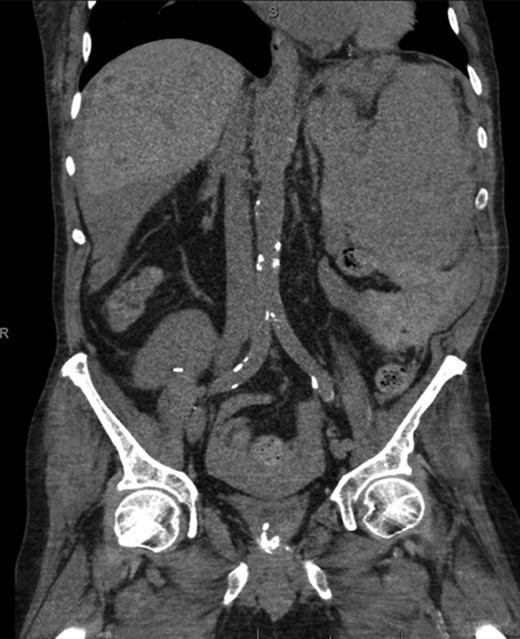

A 68-year-old male with history of living donor renal transplant presented to the ED with acute onset of profound weakness, fatigue, left upper quadrant abdominal pain, hypotension and lactic acidosis. On exam, he exhibited mild left upper quadrant and epigastric tenderness without evidence of peritonitis. CT imaging demonstrated splenomegaly with a large splenic hematoma measuring 15.7 × 9.2 × 12 cm and associated hemoperitoneum (Figs 1–3). In addition, innumerable osseous lytic lesions were identified. Given these findings, emergent surgical consultation was obtained and his coagulopathy reversed. He remained hypotensive despite resuscitation, thus was taken for laparotomy. Upon abdominal entry, a large amount of old clot was evacuated. The abdomen was packed in all quadrants in the standard fashion. Upon removal of the left upper quadrant packs, active hemorrhage began to well from the region of the spleen which was mobilized and removed via splenectomy. Upon gross inspection, the spleen was hyperemic and abnormally indurated, with an avulsion type injury extending several centimeters across the inferior pole. There was no evidence of pseudoaneurysm or other gross pathology. Given the patient was mildly hypothermic and coagulopathic with continued oozing from the retroperitoneum, the decision was made to pack the splenic fossa and place a temporary wound vac. The patient was transported to the ICU for resuscitation and brought back to the OR the next morning for re-exploration and closure. Despite hemodynamic stabilization, he underwent a prolonged hospitalization complicated by atrial fibrillation, renal allograft failure, VAP, and ultimately PEA arrest progressing to asystole. He died 6 weeks following splenectomy. The pathology from the spleen revealed splenomegaly with parenchyma that was replaced with amorphous and acellular eosinophilic material. Histologic staining (Thioflavin-T) was positive for amyloidosis, AL-type. Oncology was consulted based on these findings with concern for lymphoproliferative disorder given osseous findings on CT, splenic pathology, and history of immunosuppression. Bone marrow biopsy was subsequently obtained which showed more than 50% atypical plasma cells/plasma blasts (CD138+; PAX5 negative; EBV (EBER) negative) and no amyloidosis, consistent with multiple myeloma. Urine showed Bence-Jones protein. Serum immunofixation studies were remarkable for a monoclonal IgG lambda gammopathy, consistent with the diagnosis of AL amyloidosis associated with systemic myeloma.

Axial CT imaging of the pelvis demonstrating heterogeneous fluid (blood) in the pelvic small bowel mesentery. Also shown is the patient’s renal transplant with clear perinephric fat planes. The renal graft was grossly uninvolved and viable appearing at the time of laparotomy.